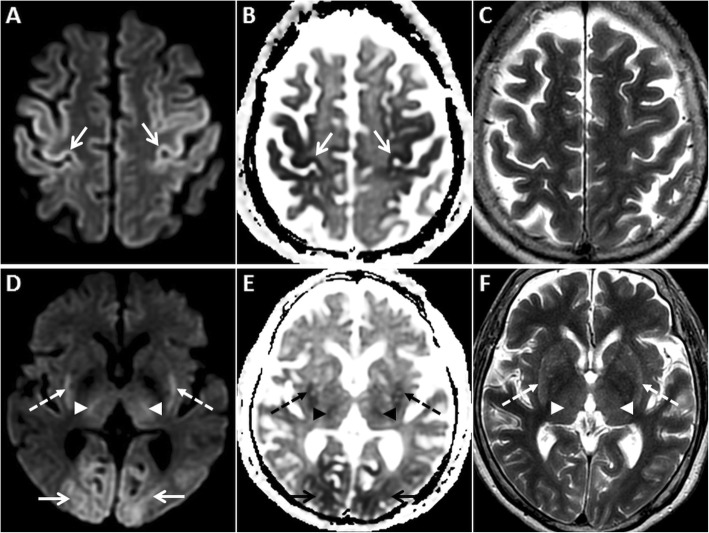

Fig. 1.

MRI of the brain performed in the acute phase of HIE. On axial DWI (a, d) and axial ADC images (b, e), symmetric GRD is seen in the perirolandic cortices (arrows in a and b) and in the visual cortices bilaterally (arrows in d and e). Restricted diffusion is also observed in the putamina (dashed arrows in d and e) and in the thalami (arrowheads in d and e). Corresponding axial T2W images (c, f) demonstrate no obvious signal abnormality in the cortices. However, there is mild T2 hyperintensity in the putamina (dashed arrows) and in the thalami (arrowheads) (f)

Fig. 2.

MRI of the brain performed in the subacute phase of HIE. DWI hyperintensity is noted in the deep grey nuclei and extensively in the cerebral cortices (arrows) on axial DWI image (a). There is no signal drop on axial ADC image (b). Diffuse cortical swelling and signal changes (arrows) are appreciated better on the axial T2W image (c). Minimal intraventricular blood (dashed arrow) is seen on axial GRE image (d). Axial source 3D-TOF MRA image (e) and reconstructed maximum intensity projection MRA image of Circle of Willis (f) show no flow signal in the intracranial arteries